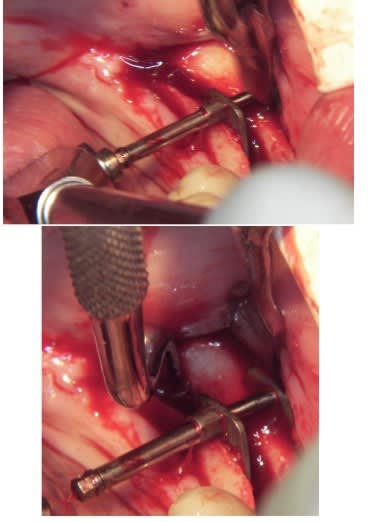

Je mets les coupes scan et tu comprendras son hésitation

pour ce vendredi, expansion verticale en bas à gauche, pas simple mais...

Implants à gauche et à droite, c’est un cas d’expansion horizontale droite et gauche que je dois faire en Novembre en directe (pour des confrères Russes), et vendredi je prépare le site à gauche, pour avoir une hauteur correcte pour remplacer ensuite 35/36.37.